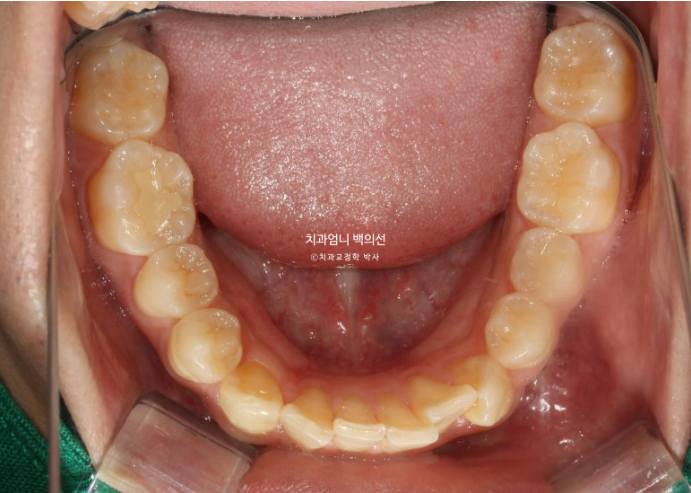

2022.10

송곳니가 많이 회전되어있고

송곳니를 포함한 앞니 치아들이 겹쳐져 있습니다.